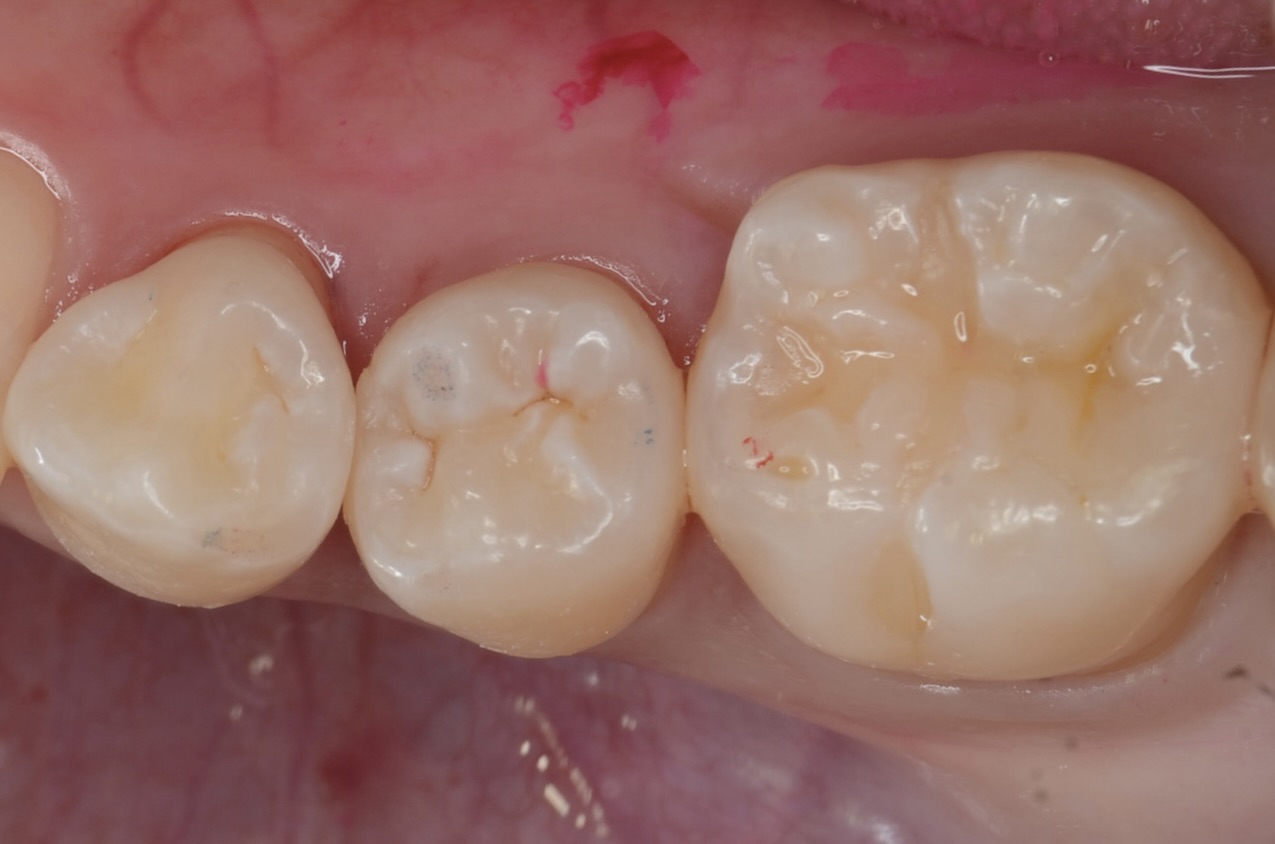

Before

| 年齢 | 40代 | 治療方法 | ダイレクトボンディング |

| 性別 | 女性 | 通院回数 | 2回 |

| 主訴 | できるだけ歯を削る量を少なくしてむし歯を治したい | 費用 |

115,500円(税込) |

| 治療のメリット | 歯を削る量を少なくできる・自然な見た目・境目がピッタリできる | ||

| 治療のデメリット | 大きい虫歯治療には適応できない場合がある | ||

調布市からお越しの患者さんです。できるだけ健康な歯を削らない治療を希望され下高井戸デンタルオフィスを受診されました。